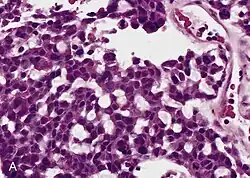

Pathology

Adrenal tumors are often not biopsied prior to surgery, so diagnosis is confirmed on examination of the surgical specimen by a pathologist. Grossly, ACCs are often large, with a tan-yellow cut surface, and areas of hemorrhage and necrosis. On microscopic examination, the tumor usually displays sheets of atypical cells with some resemblance to the cells of the normal adrenal cortex. The presence of invasion and mitotic activity help differentiate small cancers from adrenocortical adenomas.[9] Several relatively rare variants of ACC include: